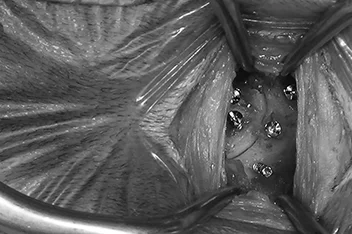

• 흉요추 디스크 MRI

• 흉요추 디스크